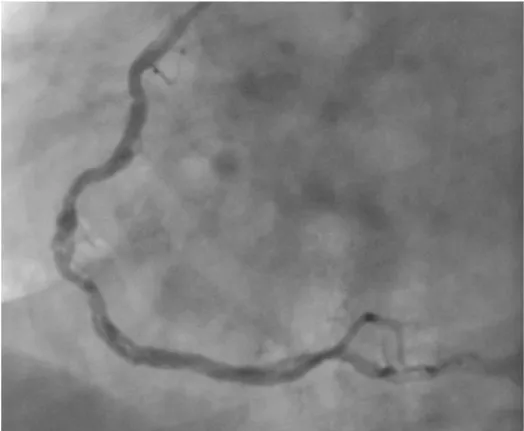

Recently, we have encountered a case of WCA associated with myocardial infarction. A 46-year-old man presented cardiology department with stable angina pectoris. An electrocardiography (ECG) showed Q waves in the inferior leads. Echocardiography examination showed akinesis of the inferior wall and left ventricle ejection fraction was 50%. The coronary angiograms showed a 70% stenosis of left anterior descending artery (LAD), 99% stenosis of circumflex artery and a twisting course of the right coronary artery lumen after it divided into multiple channels (woven right coronery artery) (Figure 1, Video1). He was transferred to the cardiovascular department for the bypass surgery.

Figure 1: Coronary angiography revealed woven coronary artery anomaly at the mid segment of the right coronary artery.

Video 1: Coronary angiography showed thin channels and distal reanastomosis of a woven coronary artery anomaly of the right coronary artery.